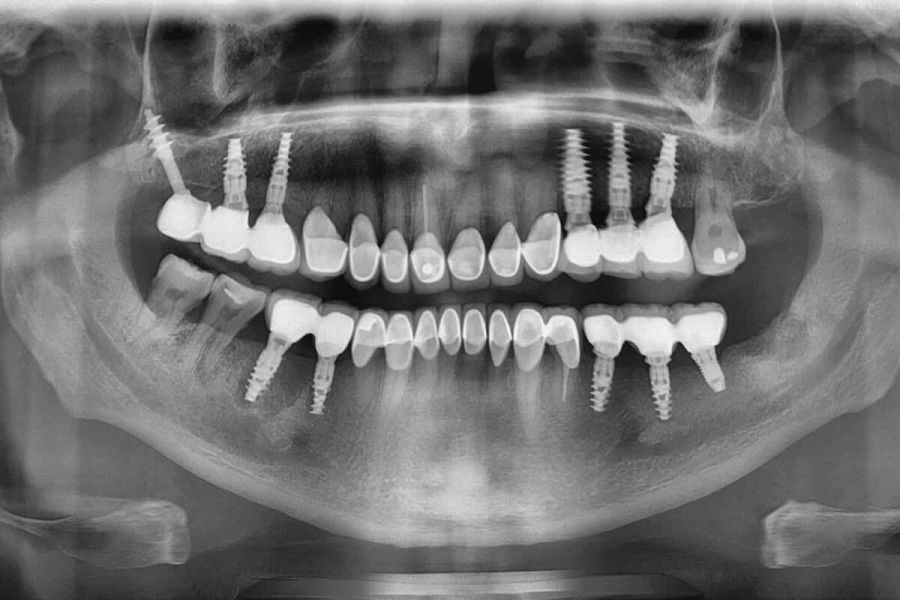

Diş implantları ağızda eksik olan dişlerin yerine konması amacıyla, genellikle titanyum veya titanyum bileşiklerinden hazırlanan yapay diş kökleridir.

Titanyum vücut dokuları ile etkileşime girmediği ve kuvvetlere karşı dirençli bir materyal olduğu için implant malzemesi olarak tercih edilir. İmplantlar daha önceden kaybedilmiş dişlerin oluşturduğu boşluklara ya da ciddi bir enfeksiyon yoksa hemen çekim sonrası diş yuvasına yerleştirilebilir.

İmplant uygulamasının asıl amacı, üzerine kullanılabilir dişler yapmaktır.

İmplantlar, sabit ya da hareketli protezler yapmak amacı ile kemiğin yeterli ve uygun olduğu durumlarda basit bir operasyonla çene kemiğine yerleştirilirler. Eğer kemik miktarı ve yoğunluğu istenilen seviyede değilse implant uygulamasından önce kemik oluşturmaya yönelik işlemler yapılması gerekebilir.